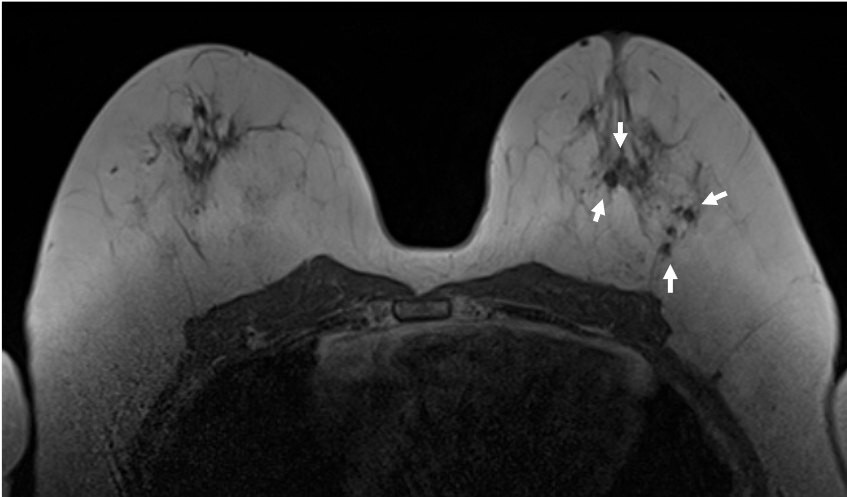

6. 造影後高分解能画像

BPEの影響が強く、観察が困難ではあるが、高分解能画像によって、内部性状(clumped)や分布(segmental)などのDCISの病変(矢印)の形態的性状がより鮮明に観察することができる。